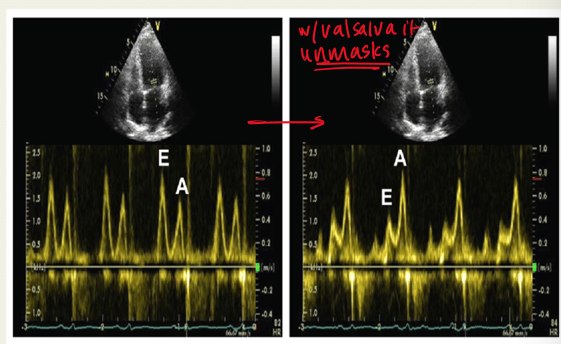

how can you differentiate normal vs moderate diastolic dysfunction

in moderate/pseudonormal : elevated atrial pressure and impaired LV relaxation

why would the mitral inflow be assessed with valsalva maneuver? explain

to unmask pseudonormal diastolic dysfunction;

valsalva decreases preload and causes E/A ratio to be less than 1